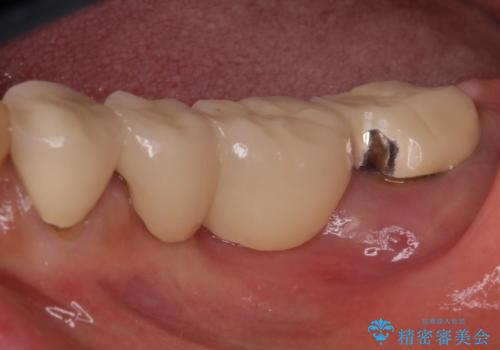

- 下顎の左右奥歯が痛みがあり、噛めないとのことで来院された患者様です。

左右ともに歯根が破折しており、抜歯が必要であったため、抜歯後にインプラント補綴治療を行うこととしました。

左上は当初治療予定ではありませんでしたが、クラウンの周りに汚れがたまっていることが気になってきたため、追加して治療を行うこととしました。

歯肉縁下にまで虫歯が及んでいたため、歯冠長延長術を行い、清掃性の改善を試みます。